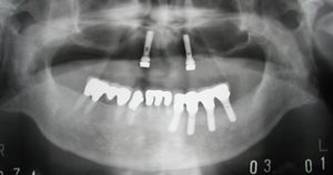

術前パノラマレントゲン写真。根の周りが黒くなり、骨がなくなっていることがわかります

治療後。歯周病で失われた骨が回復しています。使用インプラントはスプラインツイストです。

術前のパノラマレントゲン写真。仮歯を支えている4本の歯は根が残っているだけで抜歯の必要がありました。

63歳術後のパノラマレントゲン。インプラントはスプラインツイスト